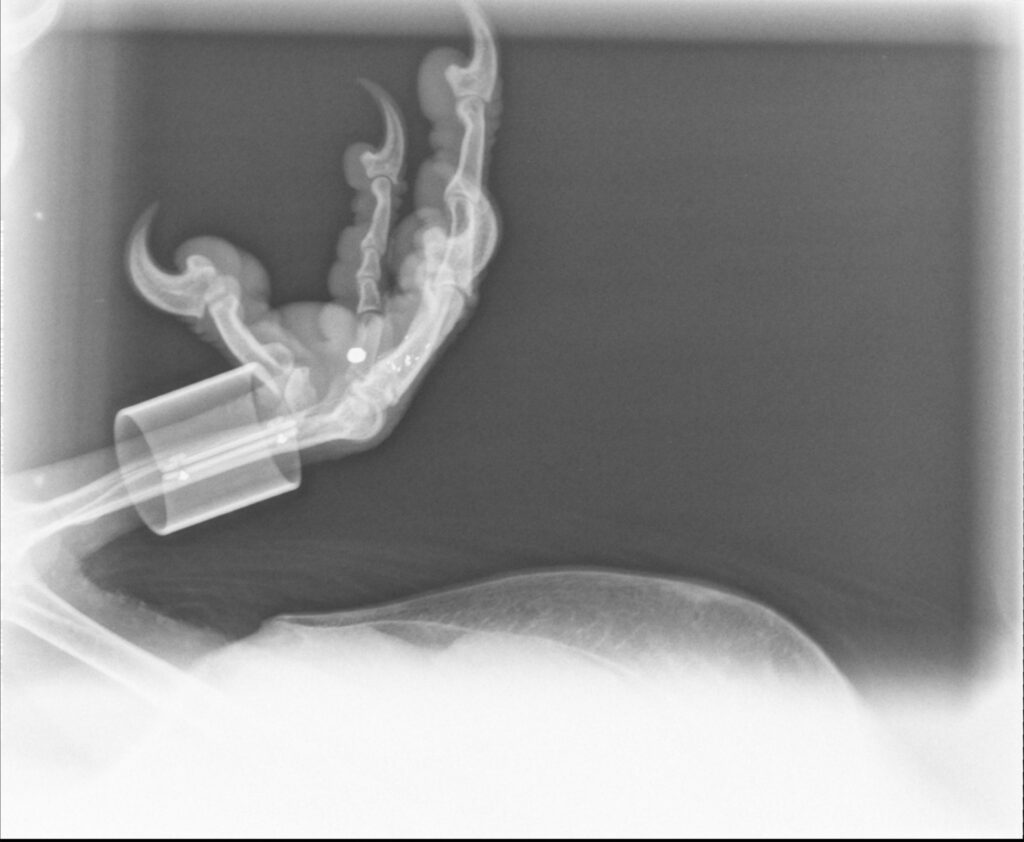

Affaibli, l’oiseau a été pris en charge par des spécialistes qui ont découvert un plomb enkysté dans sa patte, rappelant que les menaces humaines persistent malgré la protection stricte de l’espèce.

Photo. © Balthazar, J. Heuret